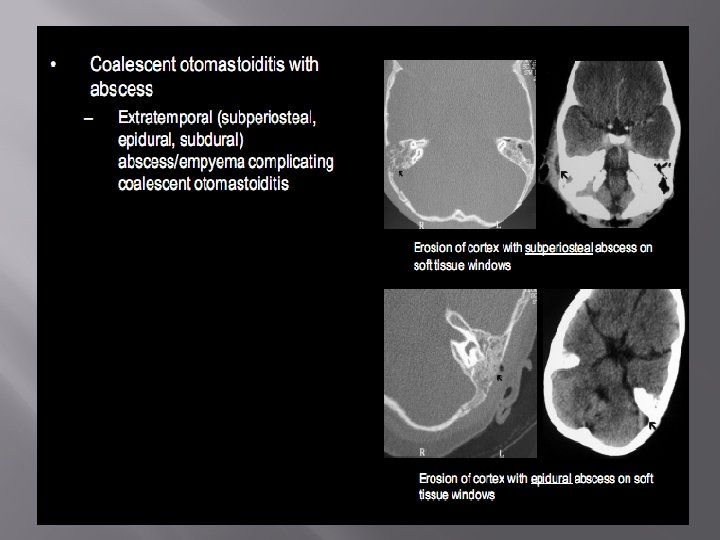

Acute otitis media and mastoiditis � � Air cell clouding Intact cell wall Fluid in middle ear No erosion in attic wall or ossicles